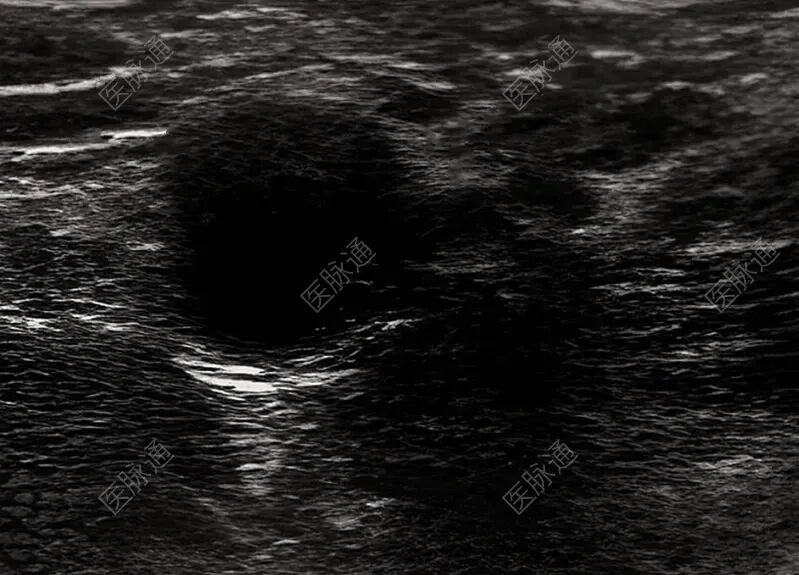

影像学显示双肾体积缩小、皮质回声增强(慢性肾实质损害),血管超声发现双下肢深浅静脉及双侧颈内静脉、锁骨下静脉广泛血栓形成,管腔充盈缺损。

图1:超声显示右侧股静脉血栓形成